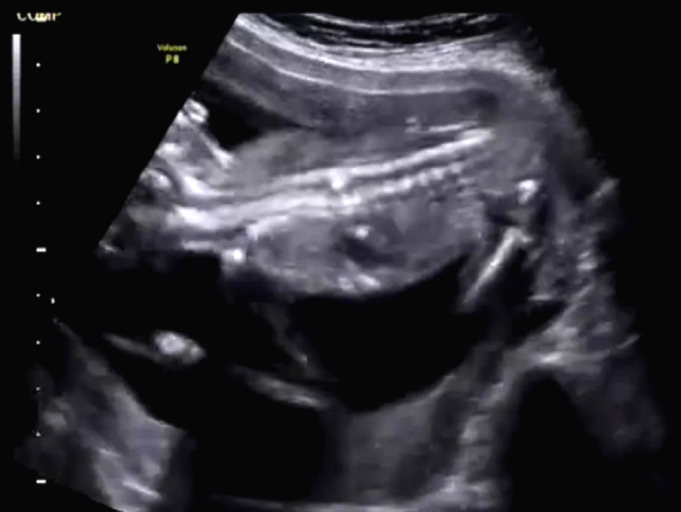

Figure 2. Second view of coronal section of the fetal spine. (Image courtesy of Firoz Bhuvar, MD)

Imaging studies: This routine transabdominal obstetric sonography was performed to exclude any congenital fetal anomalies. The patient had not undergone any sonographic study prior to this scan. The images seen in Figure 1, Figure 2, and Figure 3 show the coronal section of the fetal spine and were taken during this routine sonographic examination.

In Figures 1, 2, and 3, the volume of amniotic fluid appears normal. The fetal abdomen also shows no significant abnormality. The placenta is fundic and posterior. No retroplacental hematoma is seen.

The most prominent anatomy in these images is the fetal spine. The fetal head is to the left of the images, and the fetal lower limbs are to the right of the images. The upper cervical and thoracic spines appear normal. However, there is an abnormality within the lower thoracic vertebrae that appears as an echogenic lesion within the spinal canal. It looks linear and extends within the mid-portion of the spinal canal. We cannot further distinguish the abnormality in this region. What are the diagnostic possibilities based on these images, at this stage?

After studying the aforementioned images, there is no obvious herniation of the meninges through a dorsal or ventral defect in the spine. However, there is an obvious anomaly visible in the images of the axial section of thoracic vertebrae, which was also visible in the images of the coronal section of the thoracic vertebrae. The anomaly is some form of division of the spinal canal.

Could this be hydromyelia, which is characterized by dilation of the central canal of the spinal cord? Or is it diplomyelia, which is division of the cord into two complete halves? Diplomyelia is possible, since there is a division of the cord in the region of the affected thoracic spine.

True diplomyelia is characterized by near-total division of the spinal cord, which is not the case here. The division is localized to the affected lower thoracic spines. In addition, there is a vertical echogenic, possibly bony, septum within the affected thoracic vertebrae. This finding suggests the possibility of diastematomyelia. This condition is seen as a partial or complete bony septum or fibrous septum that divides the spinal canal (localized to affected spine), with partial division of the spinal cord in the affected parts only.